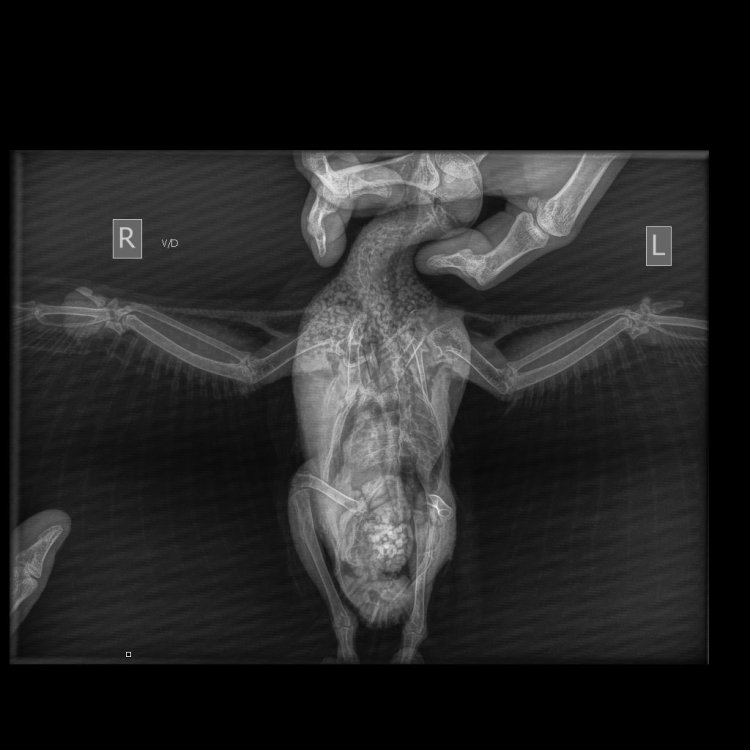

Анастасия Ст. Опубликовано 31 марта, 2025 Автор #6 Опубликовано 31 марта, 2025 Сделали в пятницу рентген в Зоогалерее на Соколе и Демина Григория. София Анатольевна видит здесь еще и зону абсцесса Броди. Но главное - нет проникновения в костную ткань, то есть это не остеосаркома. Будем колоть новокаин с чем-то в корень опухоли и антибиотик в\м. Жду назначений. 1

Cabrera Опубликовано 2 апреля, 2025 #9 Опубликовано 2 апреля, 2025 В 31.03.2025 в 11:06, Анастасия Ст. сказал: Сделали в пятницу рентген в Зоогалерее на Соколе и Демина Григория Не умеет этот человек раскладывать птиц. Прямая проекция у Вас полностью запорота. По ней невозможно оценить состояние внутренних органов. Понятно, что Вас в первую очередь интересовала опухоль, но Вы заплатили за снимок и должны были получить качественный результат, чтобы и состояние внутренних органов тоже можно было оценить. Рентген это один из основных инструментов диагностики и по нему можно увидеть многие проблемы. Опухоль очень похожа на фибролипому. Фибролипома - доброкачественная опухоль. Она имеет тенденцию постепенно увеличивается в размерах, поэтому лучше всего ее хирургически удалить у врача. Только пожалуйста, у кого-то из проверенных специалистов Маркина/Шевченко/Томашевский/Волгина (она сама не оперирует, только в паре с хирургом). Не надо колоть голубю преднизолон, не нужны птице эти эксперименты. Покажите ее очно хорошему специалисту, Вы же в Москве. Не лечите данную птицу на форуме. По поводу антибиотика. Нет таких сроков применения антибиотиков в современной медицине птиц, как 8, 10, 12 дней. Минимально возможный срок приема антибиотика 14 дней, в противном случае Вы просто вырастите резистентную микрофлору и потеряете для дальнейшего лечения все фторхинолоны. При этом даже курс в 14 дней крайне ненадёжен. Когда речь идет об инфекции костей, то это 30+ дней, не меньше.

Анастасия Ст. Опубликовано 2 апреля, 2025 Автор #10 Опубликовано 2 апреля, 2025 (изменено) 4 минуты назад, Cabrera сказал: Не умеет этот человек раскладывать птиц. Прямая проекция у Вас полностью запорота. По ней невозможно оценить состояние внутренних органов. Понятно, что Вас в первую очередь интересовала опухоль, но Вы заплатили за снимок и должны были получить качественный результат, чтобы и состояние внутренних органов тоже можно было оценить. Рентген это один из основных инструментов диагностики и по нему можно увидеть многие проблемы. Опухоль очень похожа на фибролипому. Фибролипома - доброкачественная опухоль. Она имеет тенденцию постепенно увеличивается в размерах, поэтому лучше всего ее хирургически удалить у врача. Только пожалуйста, у кого-то из проверенных специалистов Маркина/Шевченко/Томашевский/Волгина (она сама не оперирует, только в паре с хирургом). Не надо колоть голубю преднизолон, не нужны птице эти эксперименты. Покажите ее очно хорошему специалисту, Вы же в Москве. Не лечите данную птицу на форуме. По поводу антибиотика. Нет таких сроков применения антибиотиков в современной медицине птиц, как 8, 10, 12 дней. Минимально возможный срок приема антибиотика 14 дней, в противном случае Вы просто вырастите резистентную микрофлору и потеряете для дальнейшего лечения все фторхинолоны. При этом даже курс в 14 дней крайне ненадёжен. Когда речь идет об инфекции костей, то это 30+ дней, не меньше. Ничего что я все делаю по рекомендации Зоси? Вы против ее назначений и лечения? Вы сейчас кого критикуете- ее наверное? Изменено 2 апреля, 2025 пользователем Анастасия Ст.